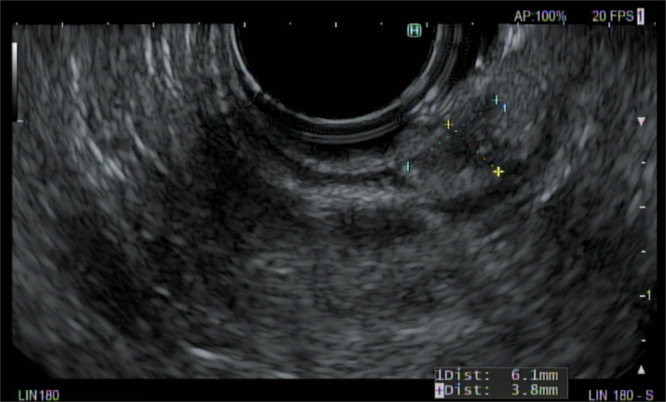

A 13-year-old with dual pancreatic rests.